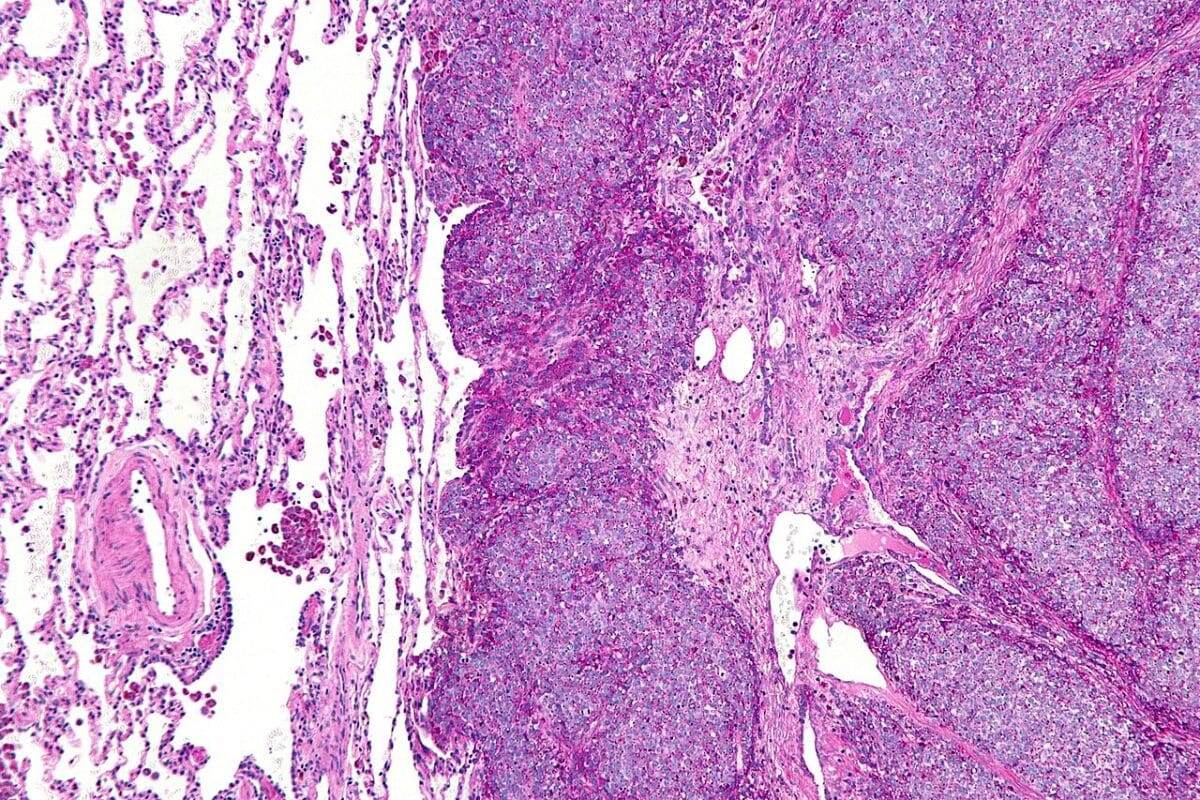

Микрография метастатической саркомы Юинга (справа на изображении) в нормальном легком (слева на изображении) / © Nephron, Wikipedia